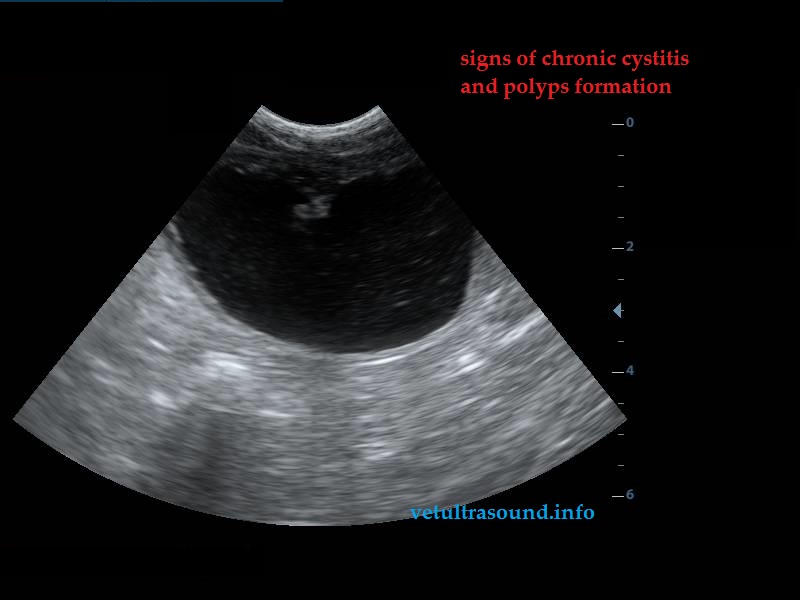

Increased echogenisity of the liver. There was no clear distinction between liver’s parenchyma and the portal’s vein wall.(pic1)

There were polyps in the urinary bladder wall and signs of cystitis.(pic4)

Έντονη αύξηση της ηχογένειας του ηπατικού παρεγχύματος. Δεν ήταν δυνατή η διαφοροποίηση του ηπατικού παρεγχύματος από το τοίχωμα της πυλαίας φλέβας.(pic1)